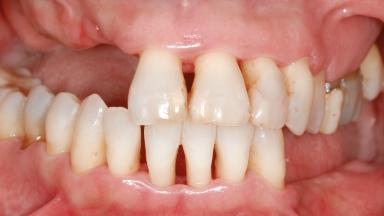

A 46-year-old woman was referred for treatment whose main complaints were mobility of her fixed partial dentures (right maxilla and left mandible) and periodontal bleeding during function. She also reported having taken systemic antibiotics to treat recurrent swelling in the area of the upper left molars. The patient had not seen a dentist for at least 2 years. She did not smoke and had no history of major systemic disease other than two minor orthopedic procedures some years back. The first-visit examination revealed poor plaque control, tooth mobility, periodontal disease, and a residual dentition widely associated with deep periodontal pockets.

Bone Volume Horizontally and vertically sufficient Horizontally deficient Deficient vertically or deficient vertically AND horizontally

Soft Tissue Contour and Volume Significantly deficient